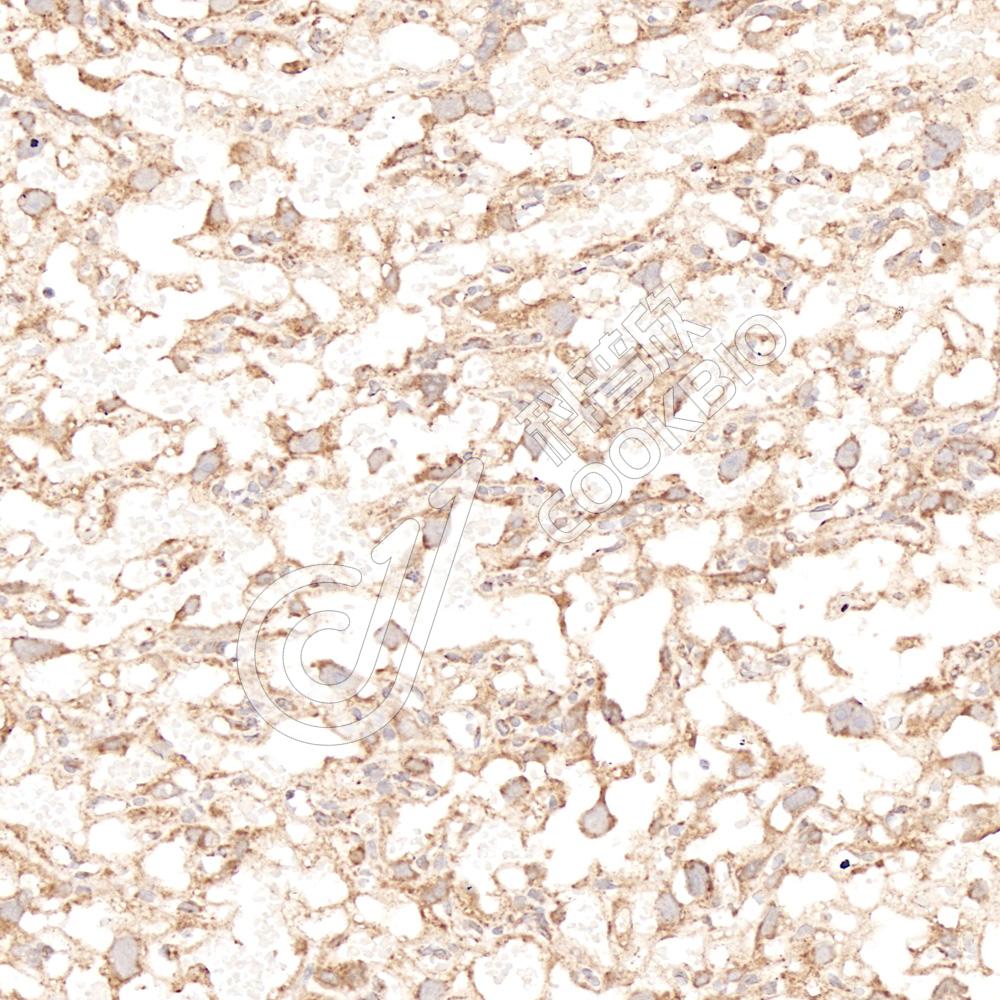

IHC检测FGF2蛋白(货号 K1341910).

样品: 人胎盘, 4%多聚甲醛 (货号KSG1101) 固定12-24小时.

抗原修复: 柠檬酸抗原修复液(干粉, pH 6.0) (KSG1201), 98℃, 20分钟.

—抗: 1: 1500稀释, 4℃ 孵育过夜.

二抗: S-vision免疫组化多聚二抗(山羊抗兔),即用型 (货号KB3906), 室温孵育20分钟.

样品: 大鼠胎盘, 4%多聚甲醛 (货号KSG1101) 固定12-24小时.